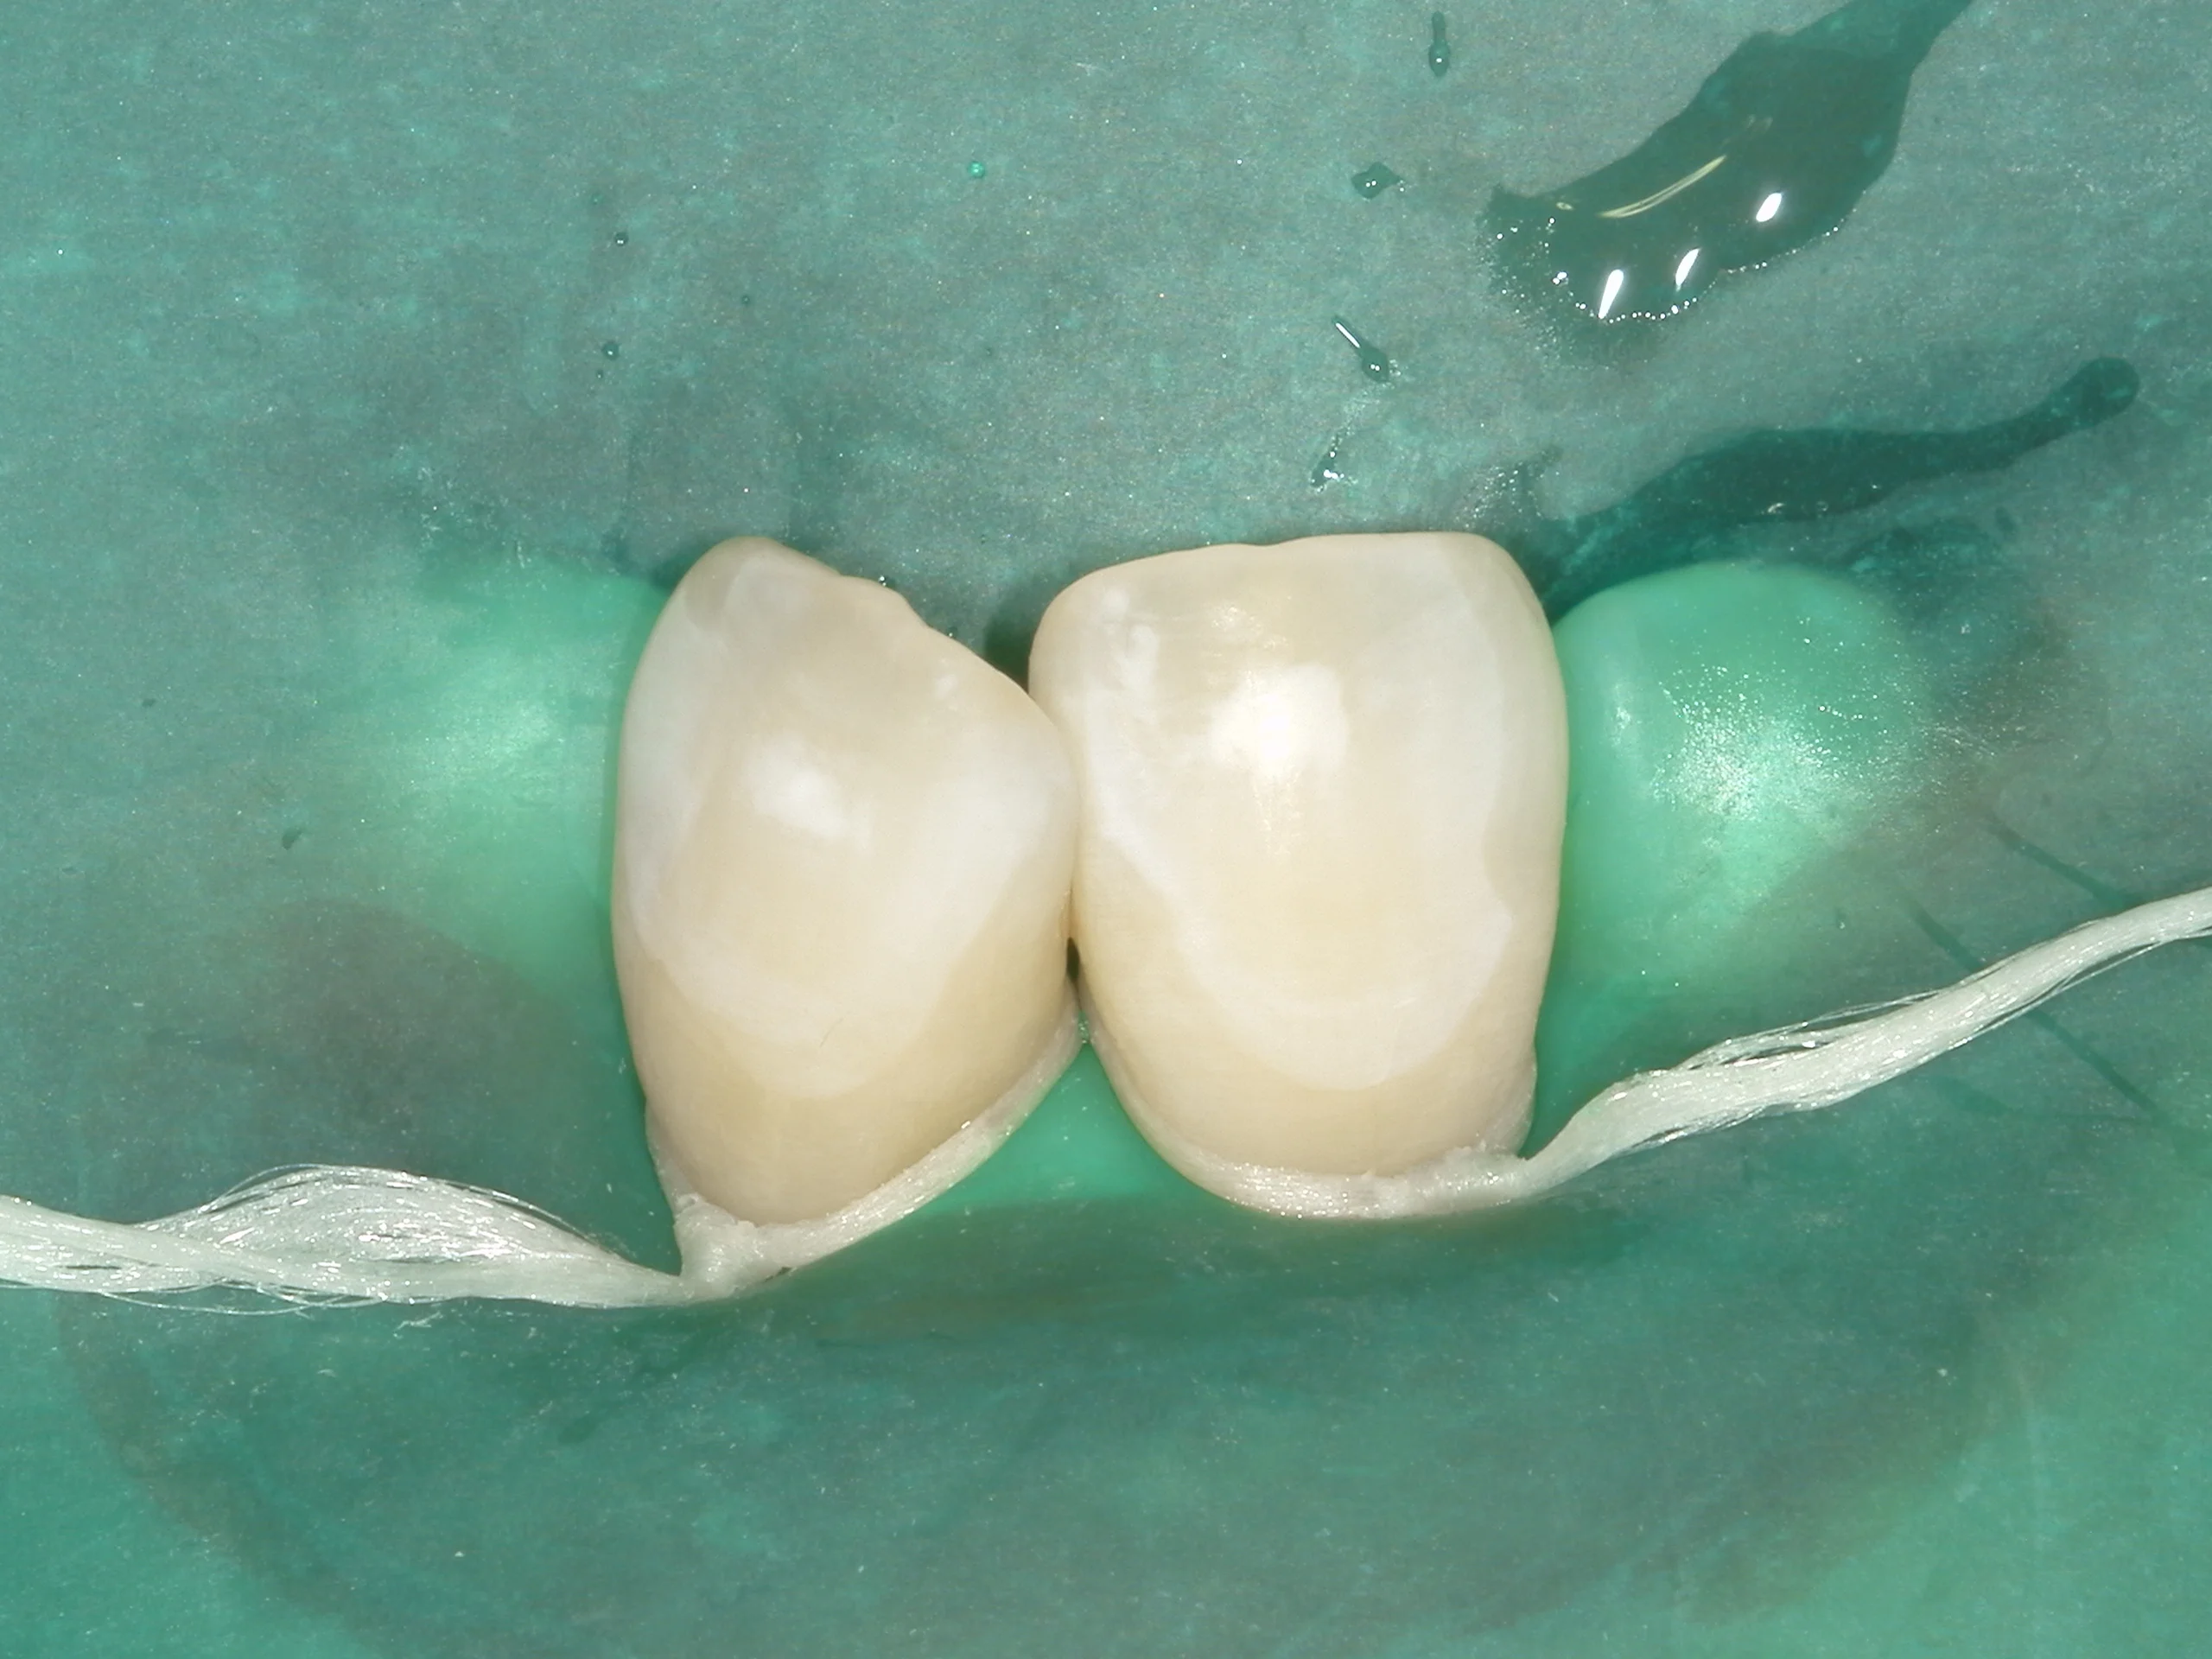

塩酸にて処理をしたのがこちらの画像になります。

何となく歯の表面が白くなってきているのが分かりますかね?

そして乾燥とエタノールによって肉眼的に確認してます。

この時にホワイトスポットが消えていなければ再度同じ動きをします。

歯質への影響を考え3回までとなっています。

1回目の段階で殆ど消えなかったら、一部歯の表面に研磨を行う必要もあります。

今回はホワイトスポットの程度が重度だったため、研磨を行った上で、薬液を使用していきました。